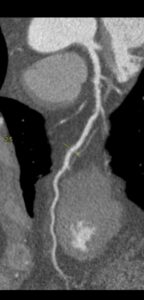

Figurile 4 si 5: reconstrucție multiplanară din examinarea recentă cu evidențierea subocluziei / ocluziei de la nivelul arterei descedente anterioare, in evolutie intre cele doua examinari